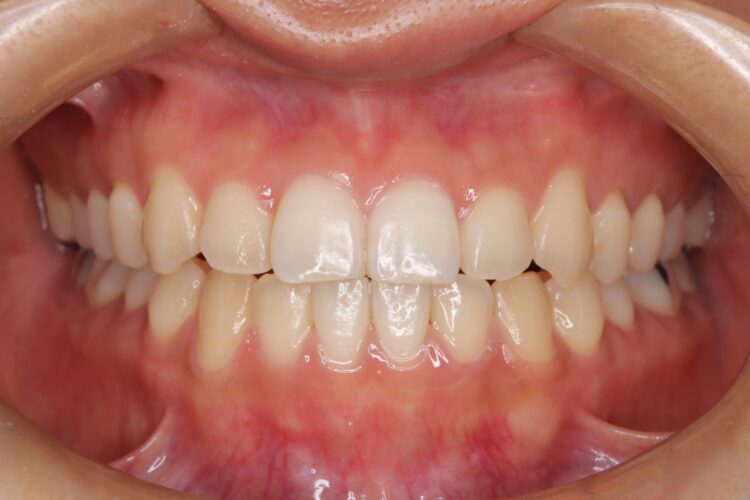

受け口の改善を主訴にご来院された患者様です。

軽度の下顎前突と診断し、マウスピース矯正装置(インビザライン)を用いて治療を行うこととしました。

治療の際はゴム掛けが必要になりましたが、患者様が非常に真面目に使用してくださったおかげで、スムーズに治療が進みました。途中の海外赴任という大きな予定変更がありましたが、そのご努力の甲斐あって、無事に渡航前に矯正を完了することができました。